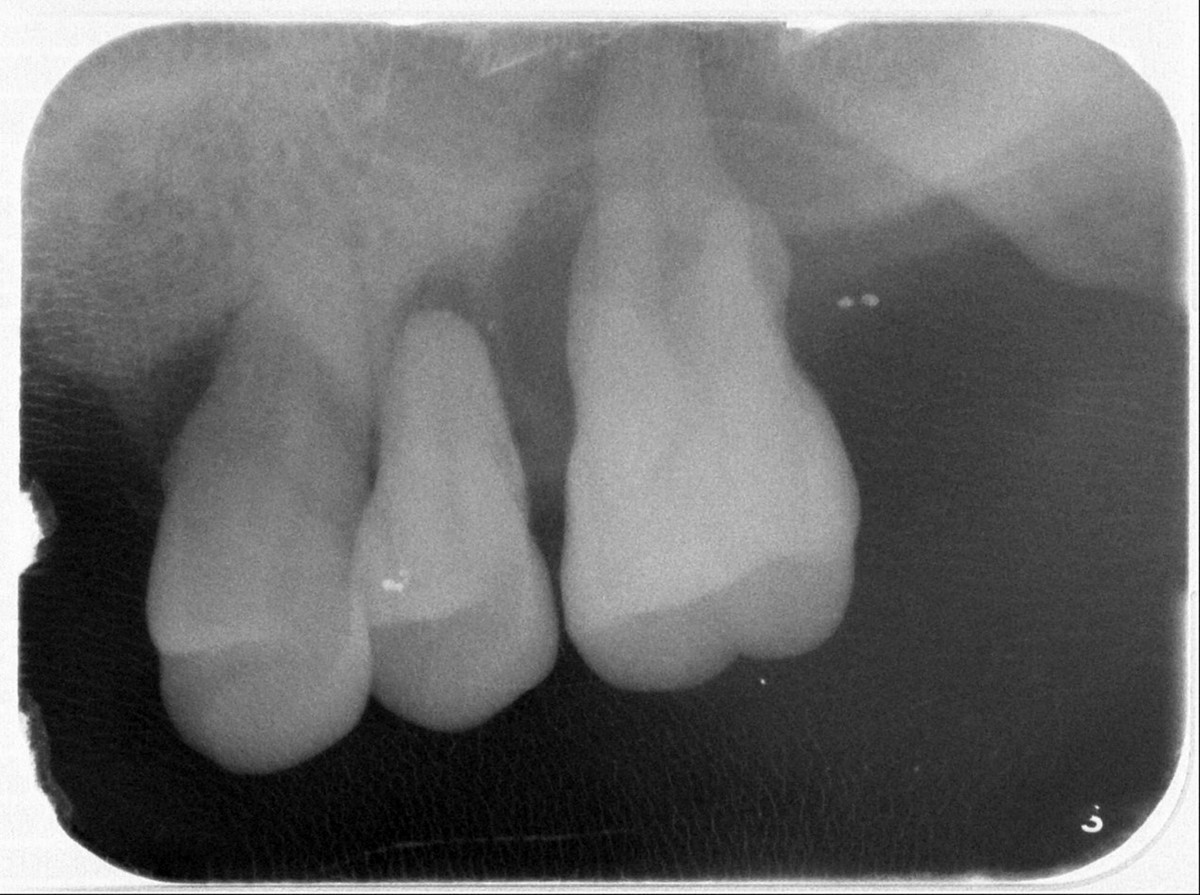

臺北榮民總醫院桃園分院牙科主任王碩26日表示,臨床上常見牙周炎症狀包括牙齦易出血、牙齦紅腫、口臭、牙齦退縮、牙根敏感與牙齒動搖等。牙周病治療前,醫師會先進行完整評估,包含量測全口牙周囊袋深度、出血點、齒齦退縮量、牙根分岔處的狀態、牙齒動搖度等指標,並搭配影像檢查。牙周病於放射線檢查,常可見水平式齒槽骨喪失,或呈狹角向根尖延伸的垂直(角形)骨缺損;骨缺損的深度與形態,不僅反映病情嚴重性,更影響後續是否能採行再生手術治療。